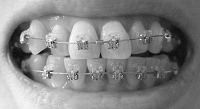

そして、ワイヤー交換。

上下とも一段階ワイヤーが太くなりました。

上の歯は、取れたブラケットを付け直してワイヤーを交換。

上下ひとつずつ、ブラケットの位置が気になっていたので先生に相談。

その2つは次回にもう一度チェックして、問題があるようなら付け替えることになりました。